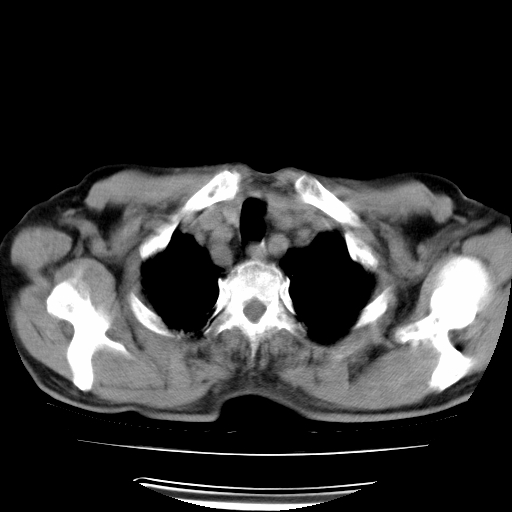

男,71岁,咳嗽,气喘10年,再发并咯血.胸片见气胸

考虑  左肺中心型肺癌伴阻塞性肺炎,肺不张,纵膈淋巴结肿大。慢支炎,肺气肿,左侧气胸肺压缩5%

左侧中央型肺癌伴纵膈淋巴结转移。

左肺中心型肺癌伴阻塞性肺炎,肺不张,纵膈淋巴结肿大

1)考虑左肺中心型肺癌伴阻塞性肺炎、左肺下叶肺不张、左侧肺气肿,纵膈淋巴结转移。2)左侧气胸(肺组织压缩约5%)。

左肺中心型肺癌伴阻塞性肺不张、肺气肿 。

1)考虑左肺中心型肺癌伴阻塞性肺炎、左肺下叶肺不张、左侧肺气肿,纵膈淋巴结转移。2)左侧气胸。